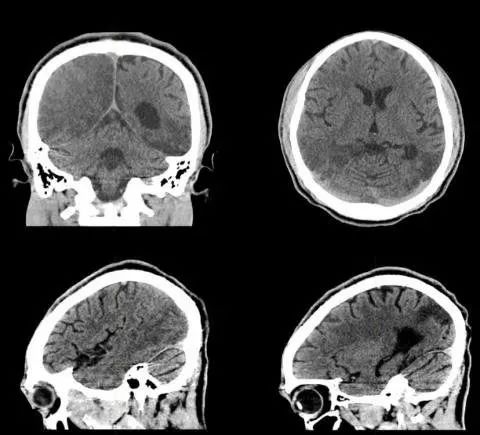

26岁,男,突发右眼视力障碍和精神状态改变入院。

11月后复查头部CT,如下图:

答案:线粒体脑肌病伴乳酸酸中毒及中风样发作(MELAS)

患者青年男性,卒中样起病,MRA未见明显异常,有好多老师想到静脉系统梗死,患者影像病灶并不符合静脉引流分布,答案是线粒体脑肌病伴乳酸酸中毒及中风样发作(MELAS)。其特征为轻度活动后即感疲乏无力,休息后好转;肌肉活检可见破碎红纤维。常以卒中样发作、痴呆、癫痫和共济失调等为主要表现。病灶影像特点与脑梗死类似,也可呈多发性、对称性、迁移性脑梗死样病变。皮层层状异常信号是其特征性影像表现。鉴别诊断有栓塞或夹层所致的真正的缺血性卒中、亚急性坏死性脑脊髓病(Leigh 脑病)、血管炎和癫痫等。